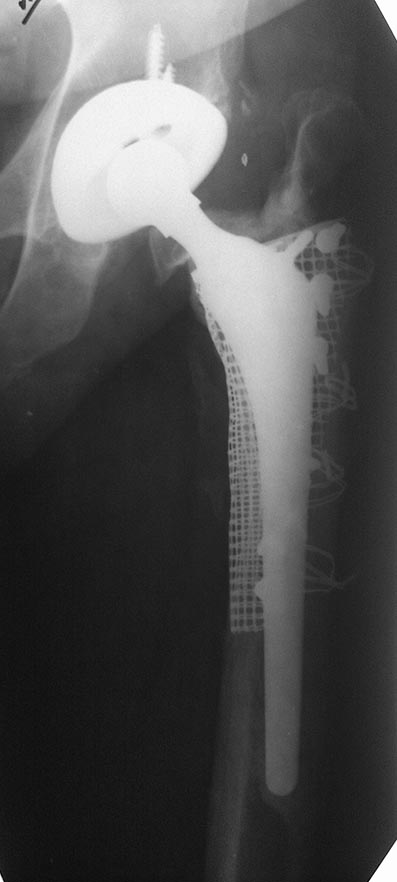

в этом случае перелом перипротезный на уровне эндопротеза с нестабильностю ножки. Это требует замены ножки. ПЛАСТИНА в любом случае требует большей инвазии. Здесь я за ножку вагнера.

Вот и было сделано нечто типа длинной ножки. Только закрыто и с запиранием.

Снимки красивые, но "люди ходят не на снимках, люди ходят на ногах". Поэтому не лишними были бы подобности типа возраста пациента, его уровня активности, хода операции (длительность, кровопотеря), ну и всякие другие небезинтересные вещи.

Не являюсь спецом по перипротезным переломам, но у нас как правило или остеосинтез или ревизионная ножка - что послужило здесь поводом сочетать оба метода?

"Операция выполнялась в соответствии со всеми принципами АО" - судя по количеству серкляжей вы с этой фразой немного погорячились. Кстати тоже: пластина позволяет вводить винты спереди и сзади от ножки протеза - почему предпочли не винты, а проволоку?

Вот случай лечения перипротезного перелома Страйкеровской сеткой. 7 лет - полет нормальный.